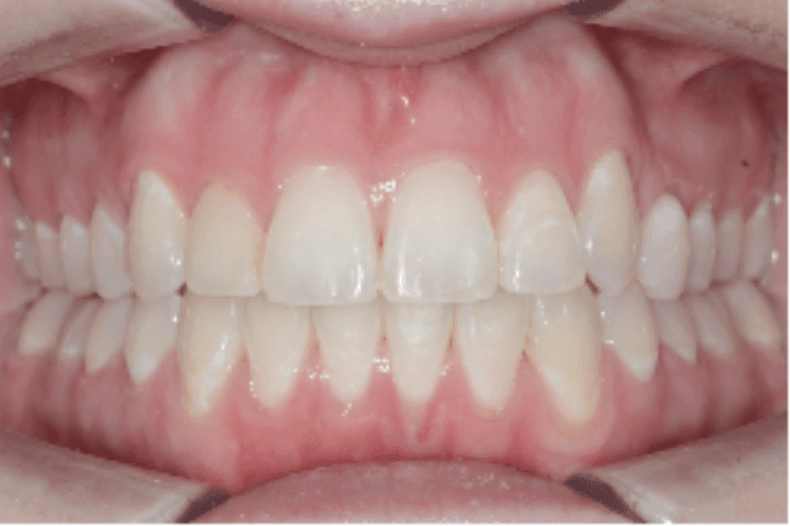

Final results

INTRAORAL